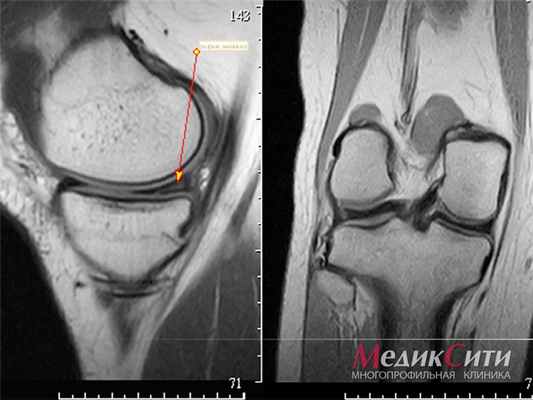

(Слева) Рентгенография в ПЗ проекции: определяется линейный склероз вдоль метафиза, отражающий консолидирующуюся линию перелома, которая распространяется от литического очага. Основание данного очага расположено в кортикальном слое кости. Это поражение неагрессивно и имеет типичные признаки НОФ. Обратите внимание, что периостальная реакция достаточно равномерно выражена и имеет плотный характер, что соотносится с консолидацией перелома.

(Справа) Рентгенография в ПЗ проекции: определяется типичный доброкачественный фиброзный кортикальный дефект большеберцовой кости. Очаг в проксимальном метафизе малоберцовой кости расположен центрально. Для НОФ характерна локализация в тонких костях. (Слева) Рентгенография коленного сустава в ПЗ проекции: у пациента, который недавно достиг скелетной зрелости, определяется литический очаг со склеротическим краем, основание которого расположено в кортикальном слое кости. Это поражение в своих более периферических отделах замещено нормальной костной тканью.

(Справа) Рентгенография в боковой проекции, этот же случай: подтверждаются наличие литического компонента с четкими контурами, а также формирование нормальной костной ткани на месте заживающего компонента поражения. Представлена типичная фиброксантома (НОФ), претерпевающая естественную эволюцию -заживление после достижения пациентом скелетной зрелости. (Слева) Рентгенография в ПЗ косой проекции: в малоберцовой кости визуализируется очаг со склеротическим краем, распространяющийся эксцентрично. Представлена НОФ на ранней фазе своего развития; по мере роста очага его расположение в данной тонкой кости будет казаться более центральным.

(Справа) МРТ, STIR, корональный срез: у этого же пациента отмечаются неоднородная интенсивность сигнала от очага и наличие в нем перегородок. Поражение содержит участки гипоинтенсивного сигнала, представляющие собой фиброзный или гемосидеириновый компоненты, а также гиперинтесивные фрагменты. МР-томограмма такого поражения является редкостью, поскольку оно обычно диагностируется по данным рентгенографии.